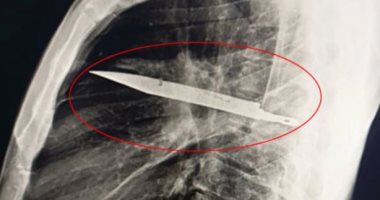

النيابة تستعلم عن الحالة الصحية للمجنى عليه فى واقعة طعن زوجته له بأكتوبر اليوم السابع منذ 1 أسبوع news